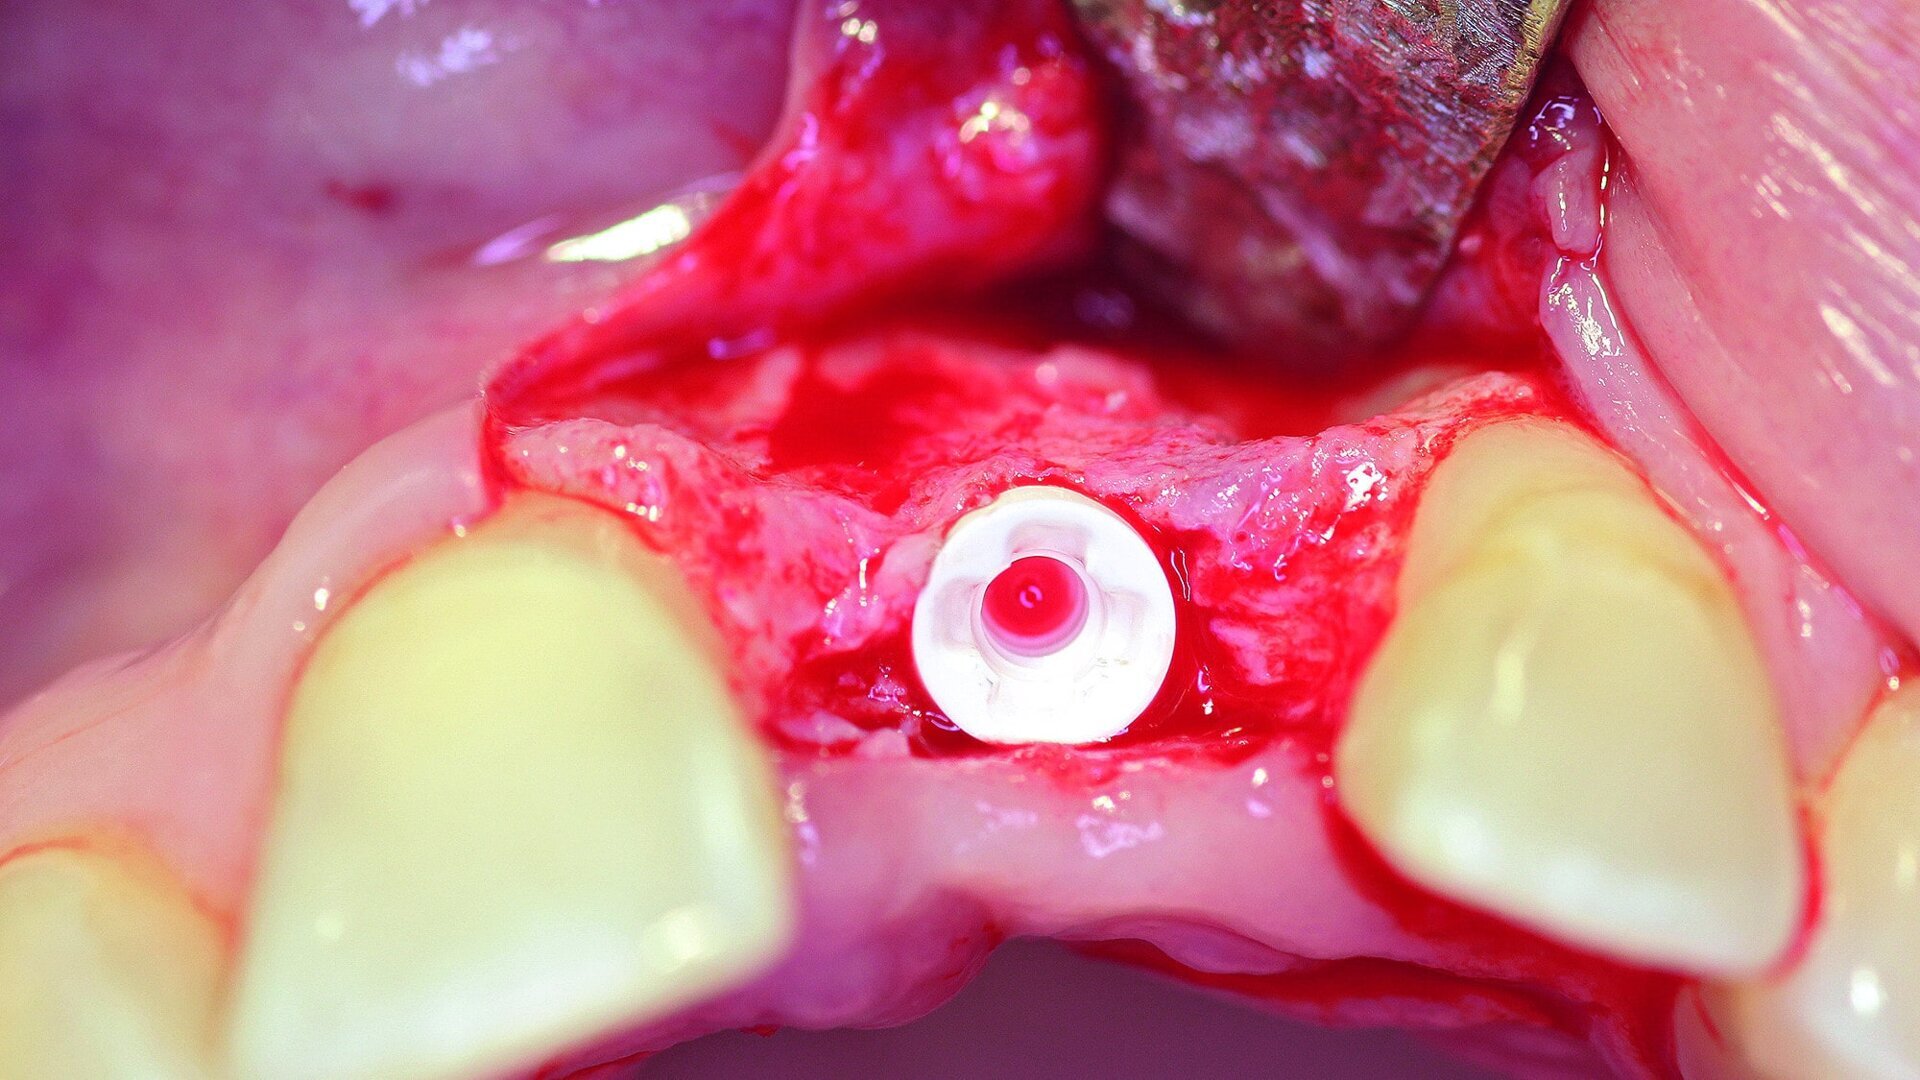

Surgical phase

After extraction of tooth #21, the apical granulation tissue was excochleated through a semilunar incision (Fig. 3). A two-stage procedure was performed to prevent failure of osseointegration of the ceramic implant and to preserve the soft-tissue structures (papillae and attached gingiva). A claspless prosthesis made from Valplast (Valplast International) served as a temporary restoration. The implant site in region #21 was uncovered after five months (Fig. 4). A two-piece ceramic implant (diameter: 4.2 mm; length: 12.0 mm) was then inserted (Figs. 5a & b). The guidelines for implant placement in the aesthetic zone and the drilling procedure specified by the manufacturer were observed.13, 14 Both vertical and transverse insertion depth are decisive for prosthetic success. The implant can be placed between 1.6 mm and 0.6 mm supracrestally because of a special thermal etching procedure in the collar region; the insertion depth is determined by the gingival height and the existing bone of the adjacent teeth. The implant positioning should be approximately 2–3 mm subgingivally because the abutments are added 1 mm above implant shoulder level. Transversal bone augmentation was performed with a mixture of autogenous bone chips (retrieved from the retromolar mandible), xenograft (Geistlich Bio-Oss, Geistlich Biomaterials) and guided bone regeneration (Jason membrane, botiss biomaterials; Figs. 6a & b). The exposure was performed after four months using a PEEK gingiva former (Fig. 7).

Fig. 3: After the extraction, the apical granulation tissue was excochleated.